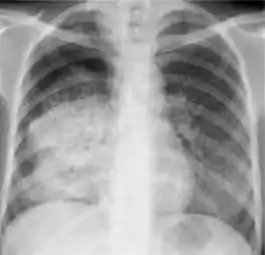

Chest x-ray showing coarse reticulonodular densities on the lower right lung of post-primary pulmonary TB.

2. Any cavitary lesion - Lucency (darkened area) within the lung parenchyma, with or without irregular margins that might be surrounded by an area of airspace consolidation or infiltrates, or by nodular or fibrotic (reticular) densities, or both. The walls surrounding the lucent area can be thick or thin. Calcification can exist around a cavity.